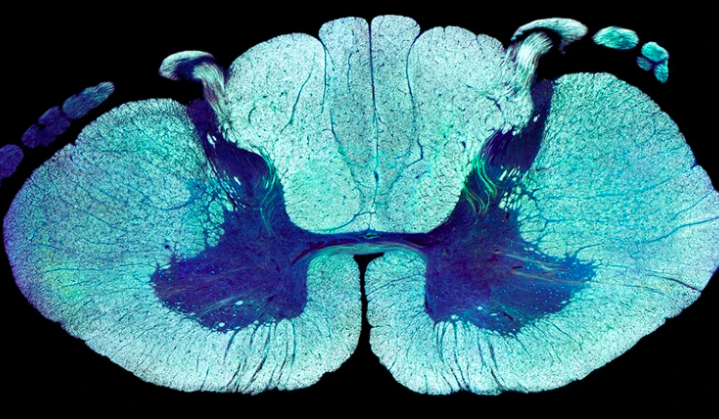

电刺激让瘫痪者重新行走原理找到了,3人已治疗成功 | Nature

「它给脊髓损伤患者带来的希望之大,简直令人难以置信。」